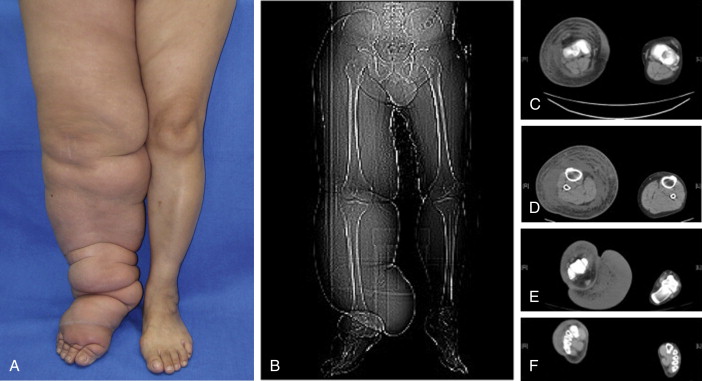

Relatively few ailments can be truly cured in medicine. Instead, we would like to propose definitions for surgical success, surgical failure, and surgical cure in lymphatic microsurgery procedures. Several staging systems exist, with the International Society of Lymphology (ISL) staging being the most accepted by the medical community so far. However, it is difficult to use the ISL staging for surgical patients, and apply it to track outcomes. Therefore, we propose a grading system, as shown in Table 23.1 , for preoperative and postoperative assessment based on objective observations including circumferential differentiation, lymphoscintigraphy, episodes of cellulitis in the last year, and quality of life. This grading system provides easy communication between surgeon and patient, and between healthcare professionals. Surgical success can be defined as the downgrading of the patient’s lymphedema with at least 10% circumferential differentiation decrease, with improved symptoms, decrease in episodes of cellulitis, and improved quality of life. Surgical failure can be defined as the inability to improve the symptoms and quality of life, including worsening them. Surgical cure can be defined as a return to normal limb circumference and ability to wean off compressive therapy—in other words, not curing the lymphatic pathology, rather restoring a physiologically compensated limb and return to normal quality of life with surgery. Figure 23.1 shows representative grading examples, also depicting the clinical improvement that can be seen with downgrading.

| Grade | CD | Lymphoscintigraphy | Episode of Cellulitis in the Last Year | ICG Pattern | Options for Management |

|---|---|---|---|---|---|

| 0 | < 9% | Partial obstruction | 0–1 | Linear | CDT |

| I | 10–19% | Partial obstruction | < 2 | Linear, splash | CDT, LVA, liposuction |

| II | 20–29% | Total obstruction | 2–4 | Linear, splash, stardust | VLN transfer, LVA |

| III | 30–39% | Total obstruction | 4–6 | Splash, stardust, diffuse | VLN transfer with liposuction or partial excision |

| IV | > 40% | Total obstruction | > 6 | Stardust, diffuse | Excision surgery with VLN transfer |